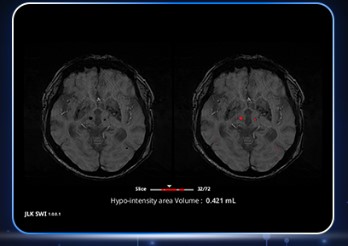

의료 인공지능(AI) 전문기업 제이엘케이는 자사의 뇌 자화(磁化)강조 자기공명영상(MRI) 기반, 즉 SWI(Susceptibility Weighted Imaging) 기반 AI 분석 솔루션이 일본 의약품의료기기종합기구(PMDA)로부터 인허가를 획득했다고 30일 밝혔다.

SWI 영상은 뇌미세출혈, 만성출혈 등 주로 뇌에 발생한 작은 출혈들을 정밀하게 보여주는 고급 영상 기법이다. 제이엘케이는 이를 AI로 자동 분석하는 기술을 개발해, 의료진들이 뇌혈관 질환·외상성 손상·퇴행성 뇌질환 등에서 신속하고 정확한 진단을 내릴 수 있도록 했다.

SWI는 뇌 내부의 미세한 출혈 흔적 등을 저신호 영역으로 나타내 아주 작은 병변도 확인할 수 있는 강점이 있다. 그러나 3차원 영상으로서 슬라이스 두께는 얇고 해상도는 높은데다가, 한번 촬영에서 생성되는 이미지 개수도 다른 영상에 비해 월등히 많아 판독에 어려움이 있었다. 의료진들은 지금까지 이를 일일히 세고 기록하는 작업을 통해 병변을 확인할 수밖에 없어 피로도와 부담이 컸던 게 현실이다.

제이엘케이의 SWI 솔루션은 이러한 어려움을 해소하고 보다 빠르고 정확하게 병변을 검출·계산할 수 있도록 지원함으로써 임상적 효용성을 크게 높인 게 특징이다. 의료진들의 피로도와 부담을 개선해 진단 프로세스를 단축시키고, 나아가 환자들의 치료까지 이르는 시간을 대폭 단축할 수 있을 것으로 전망된다.